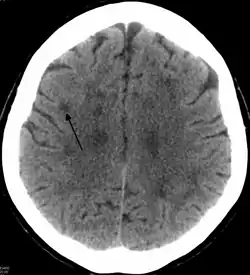

"CT showing a leukoencephalopathy "

An axial CT scan of a patient presenting a leukoencephalopathy, the base disorder to the family of disorders that HDLS falls under.

In HDLS, there is enlargement of the lateral ventricles and marked thinning or weakening of cerebral white matter.[6] The loss of white matter is caused by myelin loss. These changes are associated with diffuse gliosis, moderate loss of axons and many axonal spheroids.[1]